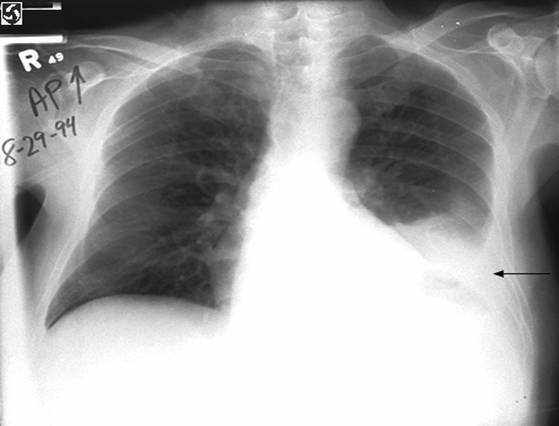

Fig. 8 Radiografie toraco-pulmonara PA -Pleurezie stanga

Opacitate de intensitate mare ce ocupa 1/2 inferioara hemitorace stang cu limita superioara usor concava superior si intern; opacitate de dimensiuni mici situata median in parenchimul pulmonar la nivelul LIS.

Mediastin in pozitie mediana. Cardiomegalie.